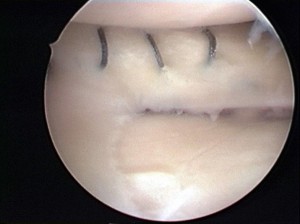

半月板縫合

半月縫合術の場合、損傷した半月に糸をかけて縫い合わせます。断裂形態により縫合の方法は変わりますが、通常は関節の中から関節の外にむけて半月板に糸をかけて縫合する方法を行っています。その場合、膝の横に約3~4cmの皮膚切開を行う必要があります。

損傷した半月板(左図)に糸をかけて縫合した状態(右図)